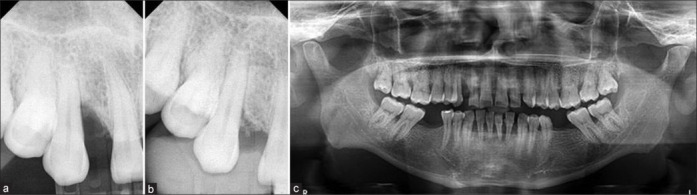

牙周骨缺损是牙科学的一大挑战,需要有效的治疗策略。本病例报告探讨了用提取牙齿的颗粒牙本质移植物(PDG)和重组人血小板衍生生长因子(rhPDGF)作为骨移植材料治疗人牙周下颌骨缺损的再生潜力。一名44岁男性患者表现为9 mm的牙袋探查深度(PPD)和8 mm的骨下缺损深度(近13 #),无牙龈退缩(GR)。在I期治疗后,进行开放皮瓣清创和PDG和rhPDGF移植。在基线、6个月和12个月进行临床和影像学测量。12个月时,观察到PPD减少6mm,临床附着水平增加,无GR。x线片显示5 mm(83.33%)骨填充。在本病例报告的限制下,利用PDG与rhPDGF治疗骨下牙周缺损已成为一种有前途的再生疗法。

Periodontal bone defects pose significant challenges in dentistry, necessitating effective treatment strategies. This case report explores the regenerative potential of using a combination of particulate dentin graft (PDG) derived from extracted teeth and recombinant human platelet-derived growth factor (rhPDGF) as bone graft material for the treatment of human periodontal infrabony defects. A 44-year-old male patient presented with a 9 mm pocket probing depth (PPD) and an 8 mm infrabony defect depth mesial to #13, with no gingival recession (GR). Following Phase I therapy, open flap debridement and grafting with PDG and rhPDGF were performed. Clinical and radiographic measurements were taken at baseline and 6 and 12 months. At 12 months, a 6 mm reduction in PPD and clinical attachment level gain were observed with no GR. 5 mm (83.33%) bone fill was seen radiographically. Within the limitations of this case report, the utilization of PDG with rhPDGF for the treatment of infrabony periodontal defects has emerged as a promising regenerative therapy.